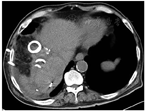

患者男性,76岁。糖尿病10余年。2015年6月11日行肝脏磁共振成像示肝脏多发占位,诊断为原发性肝细胞癌。2015年6月30日行肝细胞癌射频消融(radiofrequency ablation,RFA)+放射性粒子植入术,恢复较好。2018年12月10日因"发现肝细胞癌复发1周"于山东大学附属威海市立医院住院治疗,病变位于肝脏IIIV段,多发,最大直径超过5 cm,靠近膈肌,行肝动脉化疗栓塞术+2次微波消融(microwave ablation,MWA),复查上腹部MR提示肝细胞癌病灶得到控制。2019年7月29日复查MR提示肝细胞癌第2次复发,再次行超声引导MWA,设定功率为60 W,重叠消融作用总时间20 min,术后恢复较好,复查上腹部MR提示肝细胞癌病灶得到控制。2019年9月16日因"乏力、咳嗽1周,发热1 d"再次入住山东大学附属威海市立医院,咳大量金黄色泡沫痰,夜间卧位明显。血常规示:白细胞11.7×109/L,中性粒细胞百分比87%。丙氨酸氨基转移酶45 U/L,转肽酶88 U/L,碱性磷酸酶156 U/L,总胆红素68 mol/L,直接胆红素49 mol/L,白蛋白32.1 g/L,凝血酶原时间15.6 s。血培养、痰培养示肺炎克雷伯杆菌阳性,胸部增强CT提示右肺下叶感染性病变。气管镜提示右肺支气管黏膜炎症改变。胃镜检查提示非萎缩性胃炎伴胆汁反流。上腹部MR+磁共振胆胰管造影(magnetic resonance cholangiopancreatography,MRCP)提示肝脓肿形成并膈肌破坏、肺部感染(图1)。给予哌拉西林他唑巴坦抗感染治疗后患者咳嗽未减轻,复查腹部CT提示肝脏消融区域脓肿形成,于2019年9月30日和10月3日分别行超声引导经皮穿刺肝脓肿引流术,术后引出脓液及浑浊胆汁样液体,但咳嗽无明显缓解。患者黄疸加重,2019年10月转入山东大学齐鲁医院再次行肝内、膈下脓肿穿刺引流术,引流术后CT表现见图2。患者术后黄疸,咳嗽减轻,感染好转。痰液经实验室生化检验证实具有胆汁酸、胆红素等胆汁成分。将5 ml亚甲蓝溶液通过引流管注入,然后从口腔中咳出含有亚甲蓝的痰液,间接证实了胆管支气管瘘(bronchobiliary fistula,BBF)。2020年1月复查CT提示肝细胞癌复发,肝门部、腹膜后淋巴结转移,患者感染、黄疸加重,不适合外科手术,于2020年1月死亡。